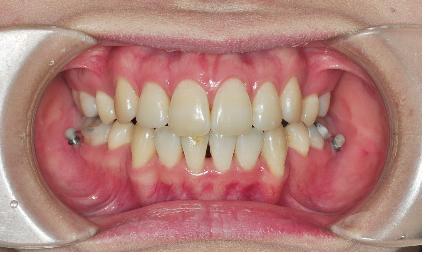

음~ 그러니깐, 제가 활짝 웃을 때 앞니부분치아가 거의 다 보이는데요,

잇몸까지는 보이지 않아요~

저는 이게 좋은 부분이라 생각하였는데 아니더라구요,

오히려 어느 정도 보여야하는 잇몸이 아예 안보인다는 것은 잇몸이 내려앉았다는것!

그래서 ‘훅’을 이용해 앞니를 올리는 치료를 하였습니다.